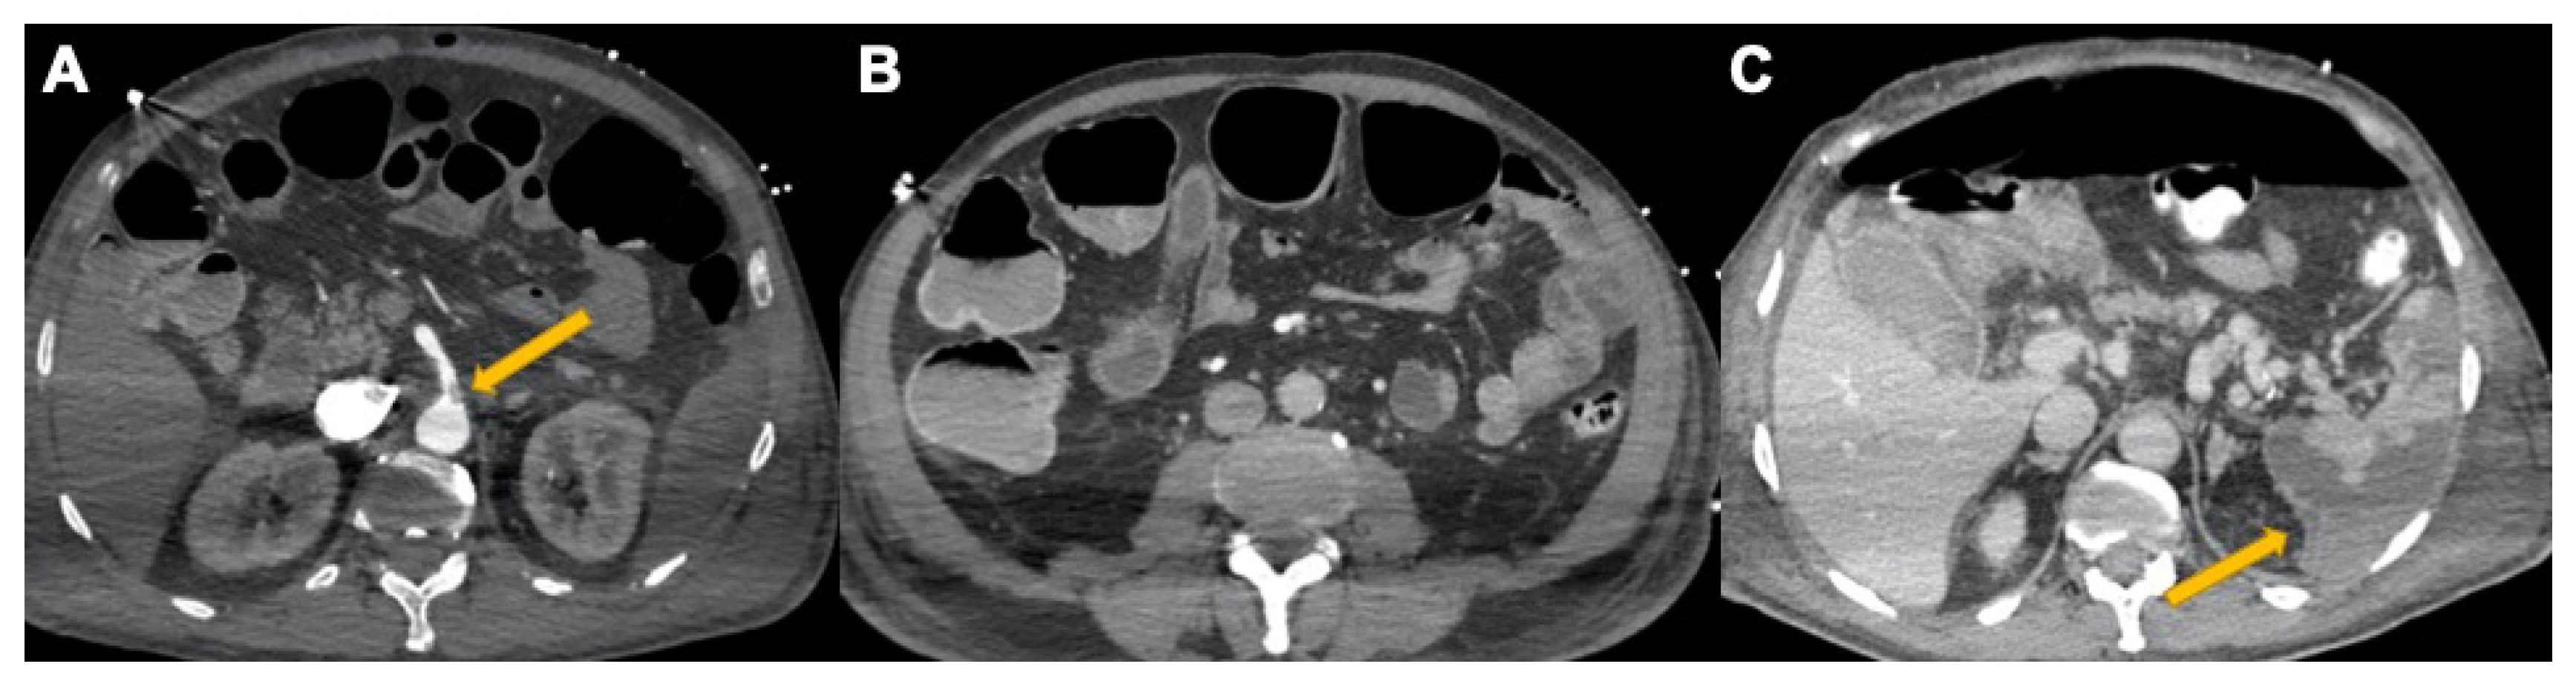

3.3. Abdominal Manifestations